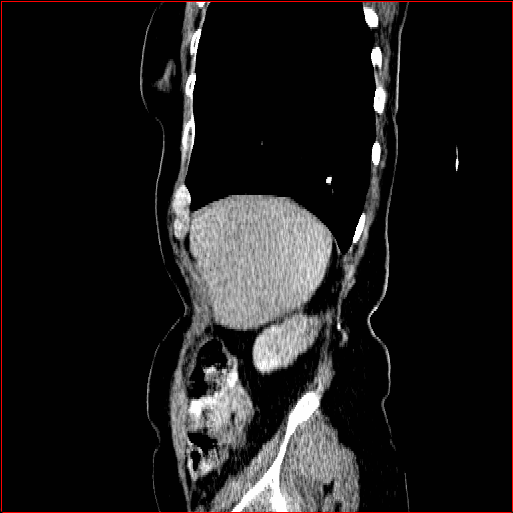

Figure 2: Qualitative comparison across axial (top row), sagittal (middle row), and coronal (bottom row) views. Columns correspond to different methods. MAISI-DDPM and MAISI-v2 in this figure are unconditional synthesis which do not use ControlNet or segmentation maps.

Qualitative Evaluation:

Figure 2 presents representative slices from the axial, sagittal, and coronal planes. GenerateCT (hamamci2024generatect) is a 2D model, so it lacks inter-slice consistency, leading to poor image quality in the sagittal and coronal views. MedSyn (xu2024medsyn) produces noticeably blurry results with mosaic-like artifacts, such as region inside the red box. HA-GAN (sun2022hierarchical) generates visually sharp images but with mosaic-like artifacts, such as region inside the red box. Also, its voxel spacing is not available, which limits its applicability in real-world medical imaging tasks. Moreover, all three methods are restricted to synthesizing small anatomical regions. In contrast, both MAISI and MAISI-v2 are capable of generating high-quality 3D volumes that span larger body regions while preserving fine anatomical details and realistic structure.